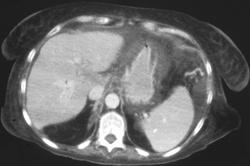

Emphysematous Gastritis With Perforation